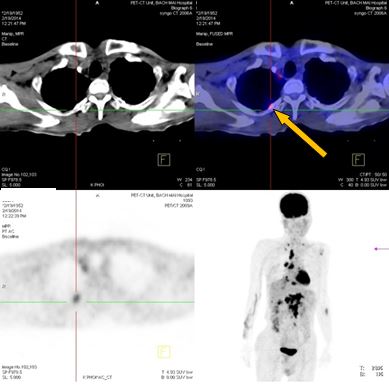

Trước điều trị: Tổn thương cung sau xương sườn số 2 bên phải, giá trị max SUV=3,13.

Sau điều trị 4 tháng: Không có bất thường

Đánh giá sau 4 tháng điều trị: Bệnh nhân đáp ứng hoàn toàn, lâm sàng cải thiện tốt, khối u và các hạch, cơ quan khác di căn tan biến. Tuy nhiên, trong quá trình bệnh nhân sử dụng thuốc, xuất hiện nổi ban ngoài da vùng mặt, ngực mức độ nhẹ. Bệnh nhân tiếp tục được duy trì Iressa 250 mg uống 1 viên / ngày.

8.Đánh giá sau 9 tháng điều trị:

Lâm sàng đáp ứng tốt, bệnh nhân không còn nổi ban ngoài da, chụp PET/ CT đánh giá lại sau 9 tháng điều trị kết quả: khối u phổi phải không còn, không còn hạch di căn, các vị trí di căn tại gan, xương biến mất.